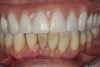

Fig 6. Periodontitis, mandibular dentition; pain and infection were evident.

Figure 6

Figure 6 represents a patient currently in a maxillary screw-retained fixed and bar-supported hybrid denture. This patient was a one-pack-a-day smoker and had severe periodontal disease and endodontic lesions for several years. The maxillary prosthesis was performing well, but the mandibular natural dentition had been deemed terminal. Consultation and examination revealed that a mandibular screw-retained prosthesis was not an option for the patient due to cost. The treatment alternative option chosen was scheduled serial extractions and immediate implant placement bilaterally in the No. 18, 20, 29, and 31 positions and in the anterior symphysis of the No. 24 to 25 region (Figure 7). An acrylic provisional treatment bridge supported by the remaining natural dentition (teeth Nos. 21, 22, 27, and 28) was fabricated at chairside, derived from a pretreatment diagnostic wax up. Four months were required to verify osseointegration of the immediately placed implants (Figure 8). After successful implant integration, a series of appointments were scheduled following traditional removable prosthetic principles to develop a removable immediate complete overdenture retained by prefabricated attachments. The definitive restoration and attachments were cold-cured intraorally. The patient was evaluated at 1 week, 3 weeks, and 3 months. To increase the stability and long-term goal of this prosthesis, the removable overdenture was reinforced by a milled metal bar for rigidity (Figure 9).